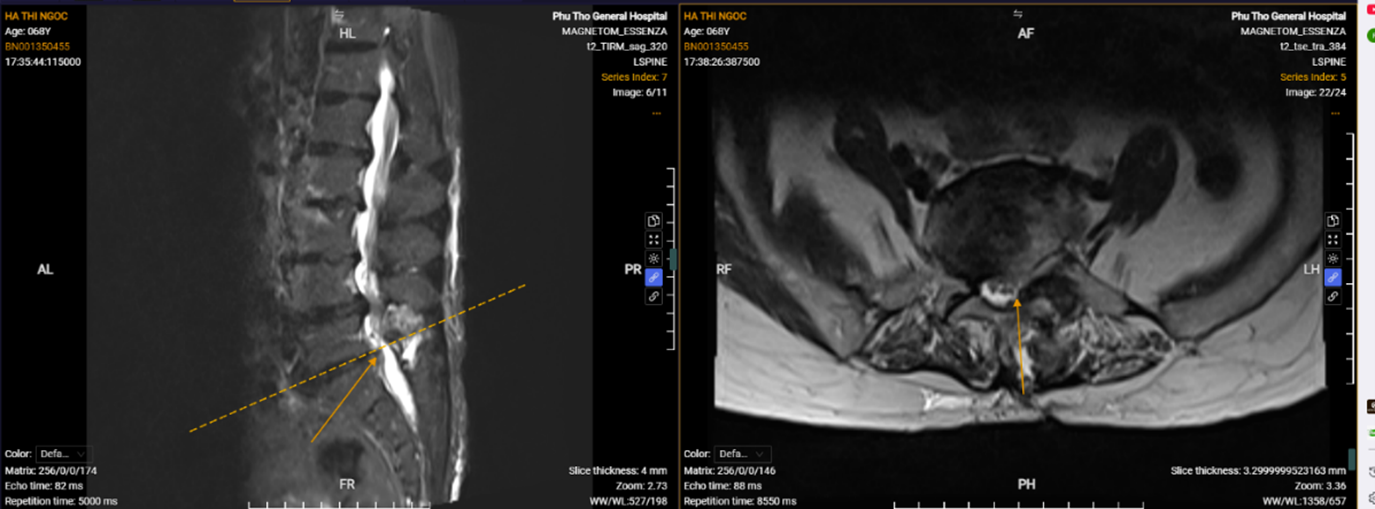

Hình ảnh phim chụp của người bệnh Hà Thị Ngọc sau phẫu thuật.

“Nhờ các bác sĩ khoa Ngoại Thần kinh tư vấn và được PGS.TS Nguyễn Văn Sơn – Phó Giám đốc Bệnh viện trực tiếp phẫu thuật, tôi gần như hồi phục hoàn toàn chỉ sau 10 ngày”. Đó là những lời chia sẻ của người bệnh Hà Thị Ngọc trước khi ra viện và người bệnh cũng không quên gửi lời cảm ơn đến PGS.TS Nguyễn Văn Sơn, BSCKII Hà Xuân Tài – Trưởng khoa Ngoại Thần kinh cùng đội ngũ bác sĩ, điều dưỡng của Bệnh viện đã tận tâm chăm sóc, điều trị cho mình trong thời gian nằm viện.